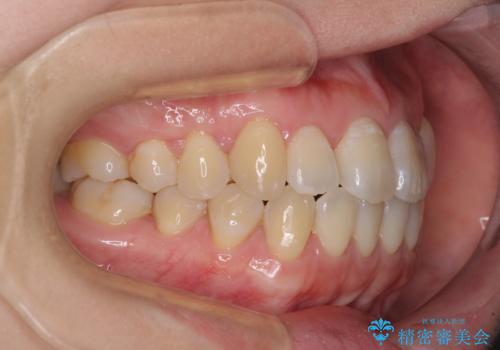

口元の突出感を改善 インビザラインによる非抜歯矯正

- 前歯がデコボコした上に口元が閉じにくいことを気にして来院された患者様です。

IPR(歯と歯の間を削る)と側方拡大では口の閉じにくさは改善できそうになく、一方で抜歯矯正を行うほどの突出感は認められませんでした。

親知らずを全て抜去し、歯列全体を後方に移動させることで口元の閉じにくさいを改善していくこととしました。

インビザラインでの歯列全体の後方移動は時間がかかりますが、しっかりと装着時間を守っていただいたので、スッキリとした口元に仕上げることができました。